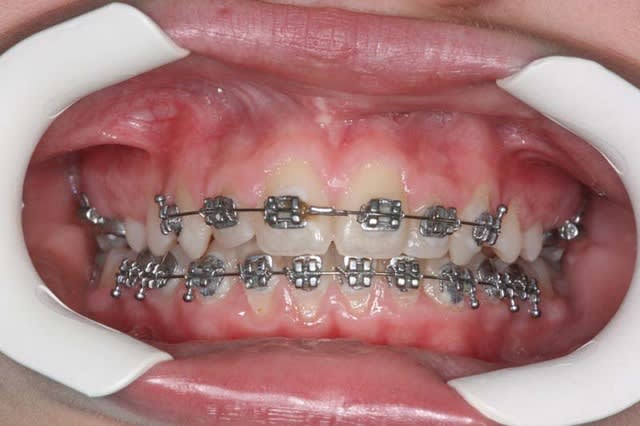

un cas traité sans bielles

@+ Bjc.

suite,

Les bielles sont difficiles à utiliser, je ne les utilise qu’en cas de micro génie, heureusement j’en ai rarement

j’obtiens le passage en Cl.I. avec seulement le reformage d’arcade, comme dans ce cas pris à la volée, (en cours de TTT).